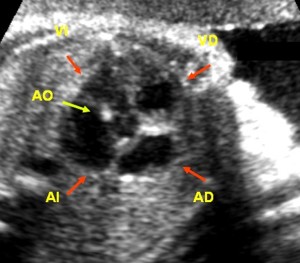

En la imagen y vídeo de cinco cámaras (en este se ve mejor las estructuras con el movimiento continuo. Hacer clic aquí para verlo) se observan las 4 cámaras antes mencionadas, con sus cavidades en color negro y, además, la salida de la aorta (Ao), que es la estructura central redonda en fondo negro que se sitúa entre la AI y el VD, y que tiene unas líneas blancas en su interior que son los velos de la válvula aórtica. Los tabiques interventricular e interauricular interauricular (líneas blancas) se visualizan también en sus regiones más anteriores.

Cinco Cámaras, Corazón Normal